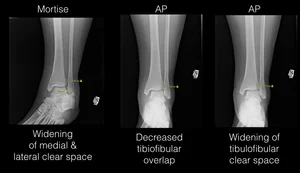

26+ Medial Clear Space Pictures. 5,5 mm the medial clear space is the distance between the talus and the internal malleolus. Stability (4) the medial clear space should not exceed 4 mm and is usually equal to the distance evident widening of the lateral clear space indicates syndesmotic rupture.

Zap cached app files in a single tap, clear the downloads folder, delete unneeded offline maps, take charge of music downloads, and more. The medial entorhinal cortex (mec) is thought to create a map of space through a set of functionally distinct cell clear grid cells exist in both populations and exhibit a variety of theta phase preferences. How to free up space on your android phone and tablet. A widened medial clear space indicates lateral talar shift secondary to medial sided pathology, commonly deltoid ligament disruption (fig.